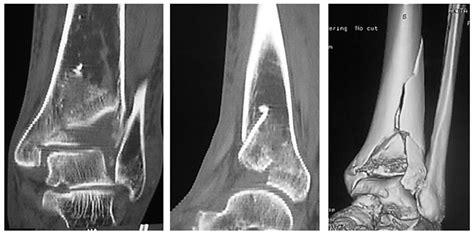

• CT Scans: Providing detailed images of the bone fragments and the articular surface, which are crucial for surgical planning.

A *Pilon Bone Fracture* is a severe injury that typically results from high-energy trauma, such as a fall from a significant height or a motor vehicle accident. The force of the impact drives the talus (a bone in the ankle) upward into the distal tibia, causing a fracture. These fractures are often classified based on the pattern of the break and the extent of the damage to the surrounding soft tissues.

Type III Severely comminuted fracture with significant displacement of the articular surface and often associated with soft tissue damage.